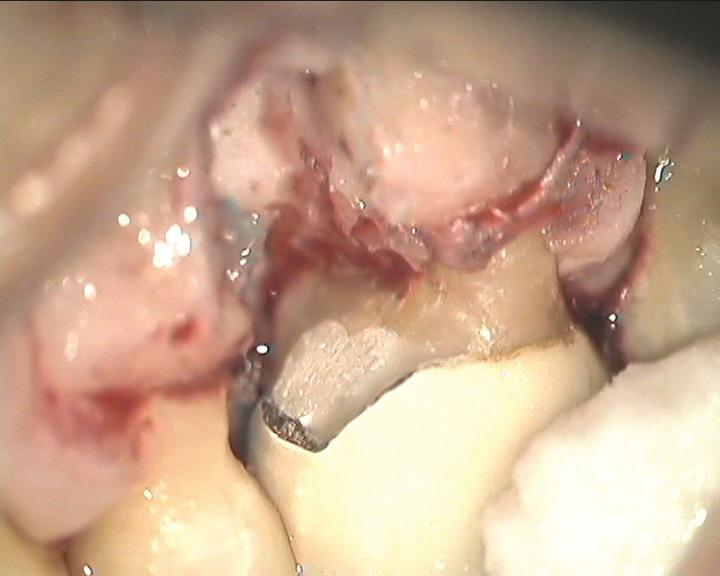

К таким патологическим состояниям относятся вертикальные переломы корней, перфорации корней, пародонтит с поражением корней из-за проблем в области фуркации или сближения корней, сочетанные эндодонтическо-пародонтальные дефекты на фоне коротких корней, устойчивые фуркационные дефекты, значительные не поддающиеся лечению внешние резорбтивные дефекты и другие (Фото 1–4). Когда подобные состояния затрагивают однокорневые зубы, удаление часто является единственным способом устранения патологии. Однако в случае многокорневых зубов существует дополнительная возможность: полное удаление источника патологии с одновременным сохранением функциональности зуба, что демонстрирует опубликованные показатели выживаемости на уровне 80–90%. При правильном выполнении с учетом описанных в статье факторов такое функциональное состояние может сохраняться в долгосрочной перспективе со средним сроком службы от 6 до 20 лет.

Фото 1: Зуб 1.6 с дистально-щечным корнем, демонстрирующим циркулярную потерю кости от уровня краевой кости до верхушки при стабильных мезиально-щечном и небном корнях.